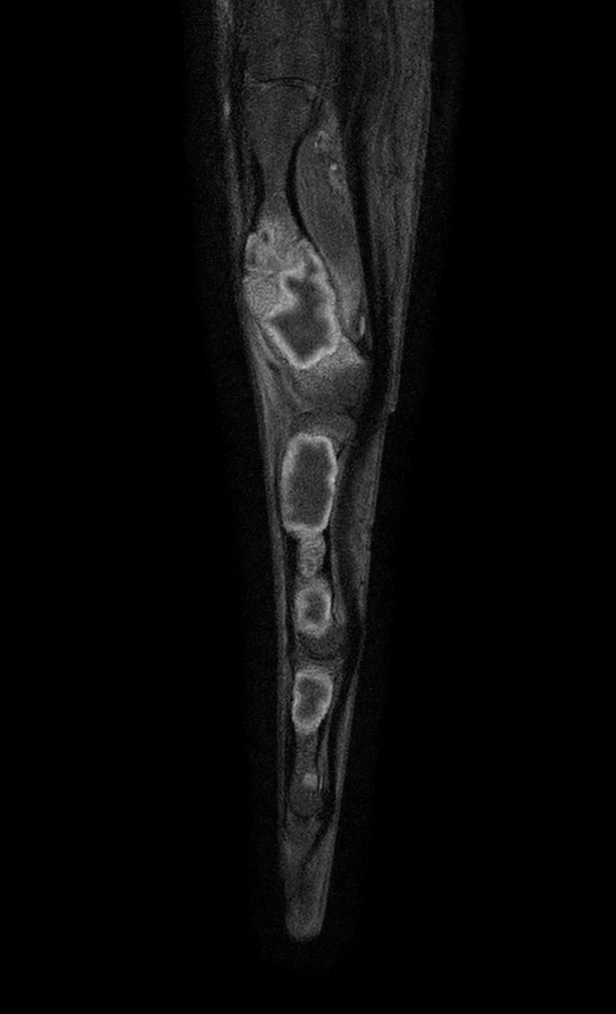

Sagittal T1w mDIXON XD TSE (Water only)

Sagittal T1w mDIXON XD TSE (In Phase)

Sagittal T1w mDIXON XD TSE (Partial FatSat)